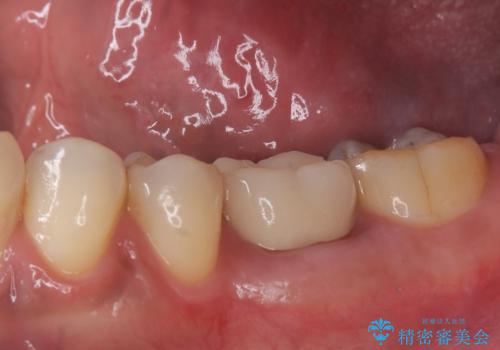

銀歯がとれた セラミックインレーで修復

- 銀歯が取れたとのことで来院されました。

拡大鏡下で丁寧に虫歯を取り除き、セラミックインレーによる修復治療を行いました。